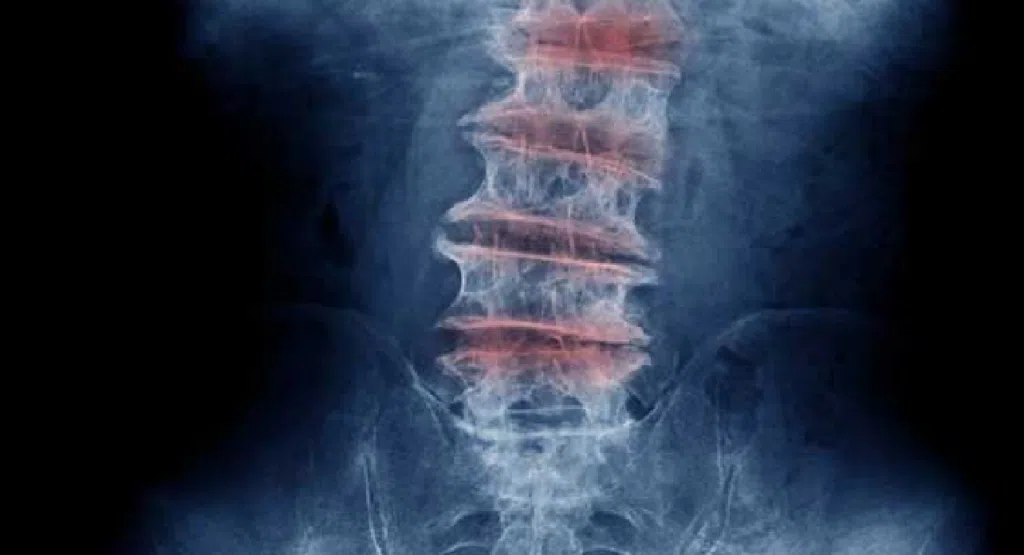

โดยทั่วไปแล้ว “อาการปวดหลัง” แบ่งออกได้เป็น 3 กลุ่มใหญ่ ได้แก่

Disk degeneration

เมื่ออายุมากขึ้น หมอนรองกระดูกสันหลังจะเริ่มหดตัว ในบางกรณีหมอนรองกระดูกสันหลังอาจยุบตัวลงจนทำให้กระดูกเสียดสีกัน ส่งผลให้เกิดอาการปวดและตึง

หมอนรองกระดูก (Intervertebral Disc) ทำหน้าที่เหมือนเบาะรองระหว่างกระดูกสันหลัง เมื่ออายุมากขึ้น หรือใช้งานหนัก หมอนรองกระดูกจะสูญเสียน้ำและคอลลาเจน ทำให้ “ความยืดหยุ่นลดลง” ผลคือเกิดการกดทับเส้นประสาท → ปวดหลัง ร้าวลงขา หรือชาบริเวณขา